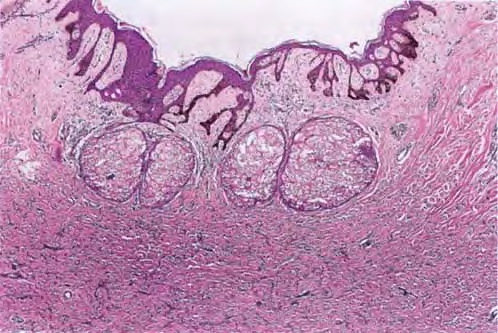

The overlying epidermis is usually acanthotic. Pseudoepitheliomatous hyperplasia and a basaloid proliferation may be noted. The hyperplasia may be caused by the action of fibroblasts on epidermal keratinocytes.23  Basal cell carcinomas occurring upon a dermatofibroma have been reported. Increased pigment may be seen, which may be iron or melanin. Most lesions display a grenz zone of normal papillary dermis overlying the tumor.

The bulk of the tumor is within the mid dermis where no capsule is present and the periphery of the lesion blends with the surrounding tissue. Whorling fascicles of a spindle cell proliferation with excessive collagen deposition are characteristic. At the periphery, the spindle cells characteristically wrap around normal collagen bundles (see the images below). Occasionally, melanocytes have been reported to be interspersed amongst the spindle cells.24